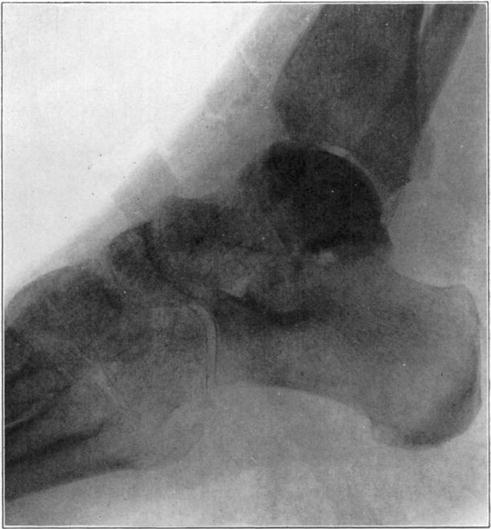

Necrosis of Os Calcis

In fracture of the neck of the os calcis the body may rarely have so much of its blood supply cut off that it undergoes extensive necrosis. Its subsequent history is analagous to that of a necrotic proximal fragment in intracapsular fracture of the neck of the femur. If bony union between the fragments follows, the necrotic body will be invaded gradually by blood vessels, fibrous, osteogenic, and myelogenous tissue, and a gradual replacement of the necrotic by living elements will be brought about. The replacement may be incomplete and the necrotic portion located farthest from the fracture may be broken down by weight-bearing before the ingrowing tissue reaches it, thereby leading to deformity and permanent derangement of the bone.

The following cases are illustrative of this condition.

Case 2. Seventy-four days after fracture of neck of astragalus, posterior dislocation of body, and reduction by operation. Body necrotic and retained normal density. Atrophy of disuse of other bones. Bony union of fracture.

Case 2. One hundred and sixty days after fracture. Body slightly reduced in density near fracture due to invasion from neck.

Case 3. Fresh fracture of neck of astragalus and chip off superior and posterior portion of os calcis.

Case 3. Two hundred and seventy-four days after injury. Fracture of astragalus united. Superior and posterior part of body broken down and irregular while remaining portion dense and transformed. Indicative of necrosis of body with secondary changes.

Case 3. Eighteen months after injury, showing a defective but gradually reforming articular portion of the body of the astragalus.

The blood supply of the astragalus is derived mainly from a branch of the arteria dorsalis pedis which traverses the sinus tarsi lateral to the neck and breaks up to enter the bone near the junction of the neck and body along the lateral and inferior surfaces. There are very small branches entering the bone mesially and posteriorly at points of ligamentous and capsular attachments. Apparently when there is a fracture along the junction of body and neck the important vessels to the body are interrupted and there may be insufficient circulation through the remaining vessels, so that aseptic necrosis of a large part or all of the fragment follows. It is evident from the partial collapse which occurred in Case 3 that when necrosis of the body is diagnosed, the limb should be protected from weight-bearing for at least several months,—until union, revascularization, and transformation of necrotic area has been largely brought about. It seems probable that some of the bad results that have been reported in fracture of the neck of the astragalus, either united or ununited, have been due to overlooked aseptic necrosis of the body.